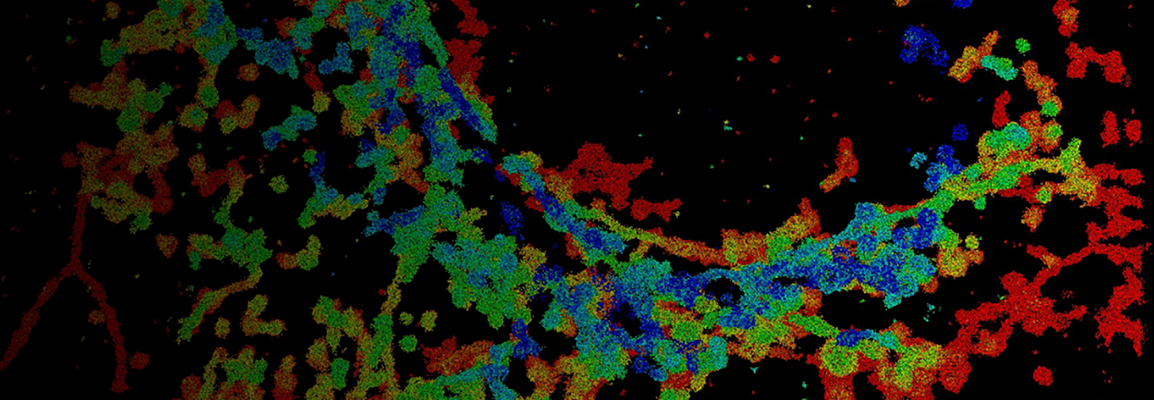

dSTORM Imaging of Neuronal GABAAR Spatial Patterning Regulated by GABA and Astrocytic Cholesterol

Understanding how membrane organization influences receptor function is a growing frontier in cellular neuroscience. In this talk, I will share how we used super-resolution direct stochastic optical reconstruction microscopy (dSTORM) imaging to uncover dynamic, lipid-dependent trafficking of γ-aminobutyric acid type A receptors (GABAARs) in primary cortical neurons. Upon GABA activation, GABAARs translocate from cholesterol-rich GM1 lipid rafts to PIP2-enriched domains, aligning temporally with receptor activation and desensitization. This translocation is disrupted by astrocytic cholesterol, resulting in receptor retention in rafts and enhanced endocytosis. Through advanced imaging, we resolved the nanoscopic movement of receptors between membrane domains and identified a cholesterol-sensitive mechanism contributing to synaptic dysfunction in neurodegeneration.